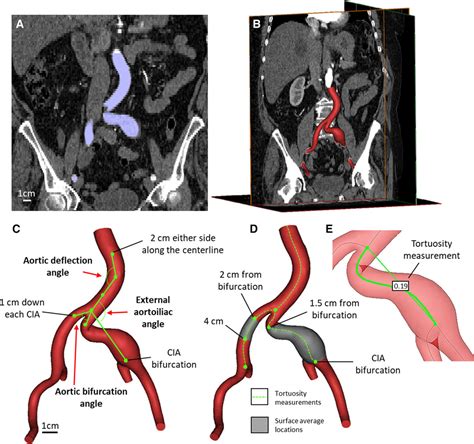

• Computed Tomography Angiography (CTA): This imaging test provides detailed images of the blood vessels and can help determine the size and location of the aneurysm.